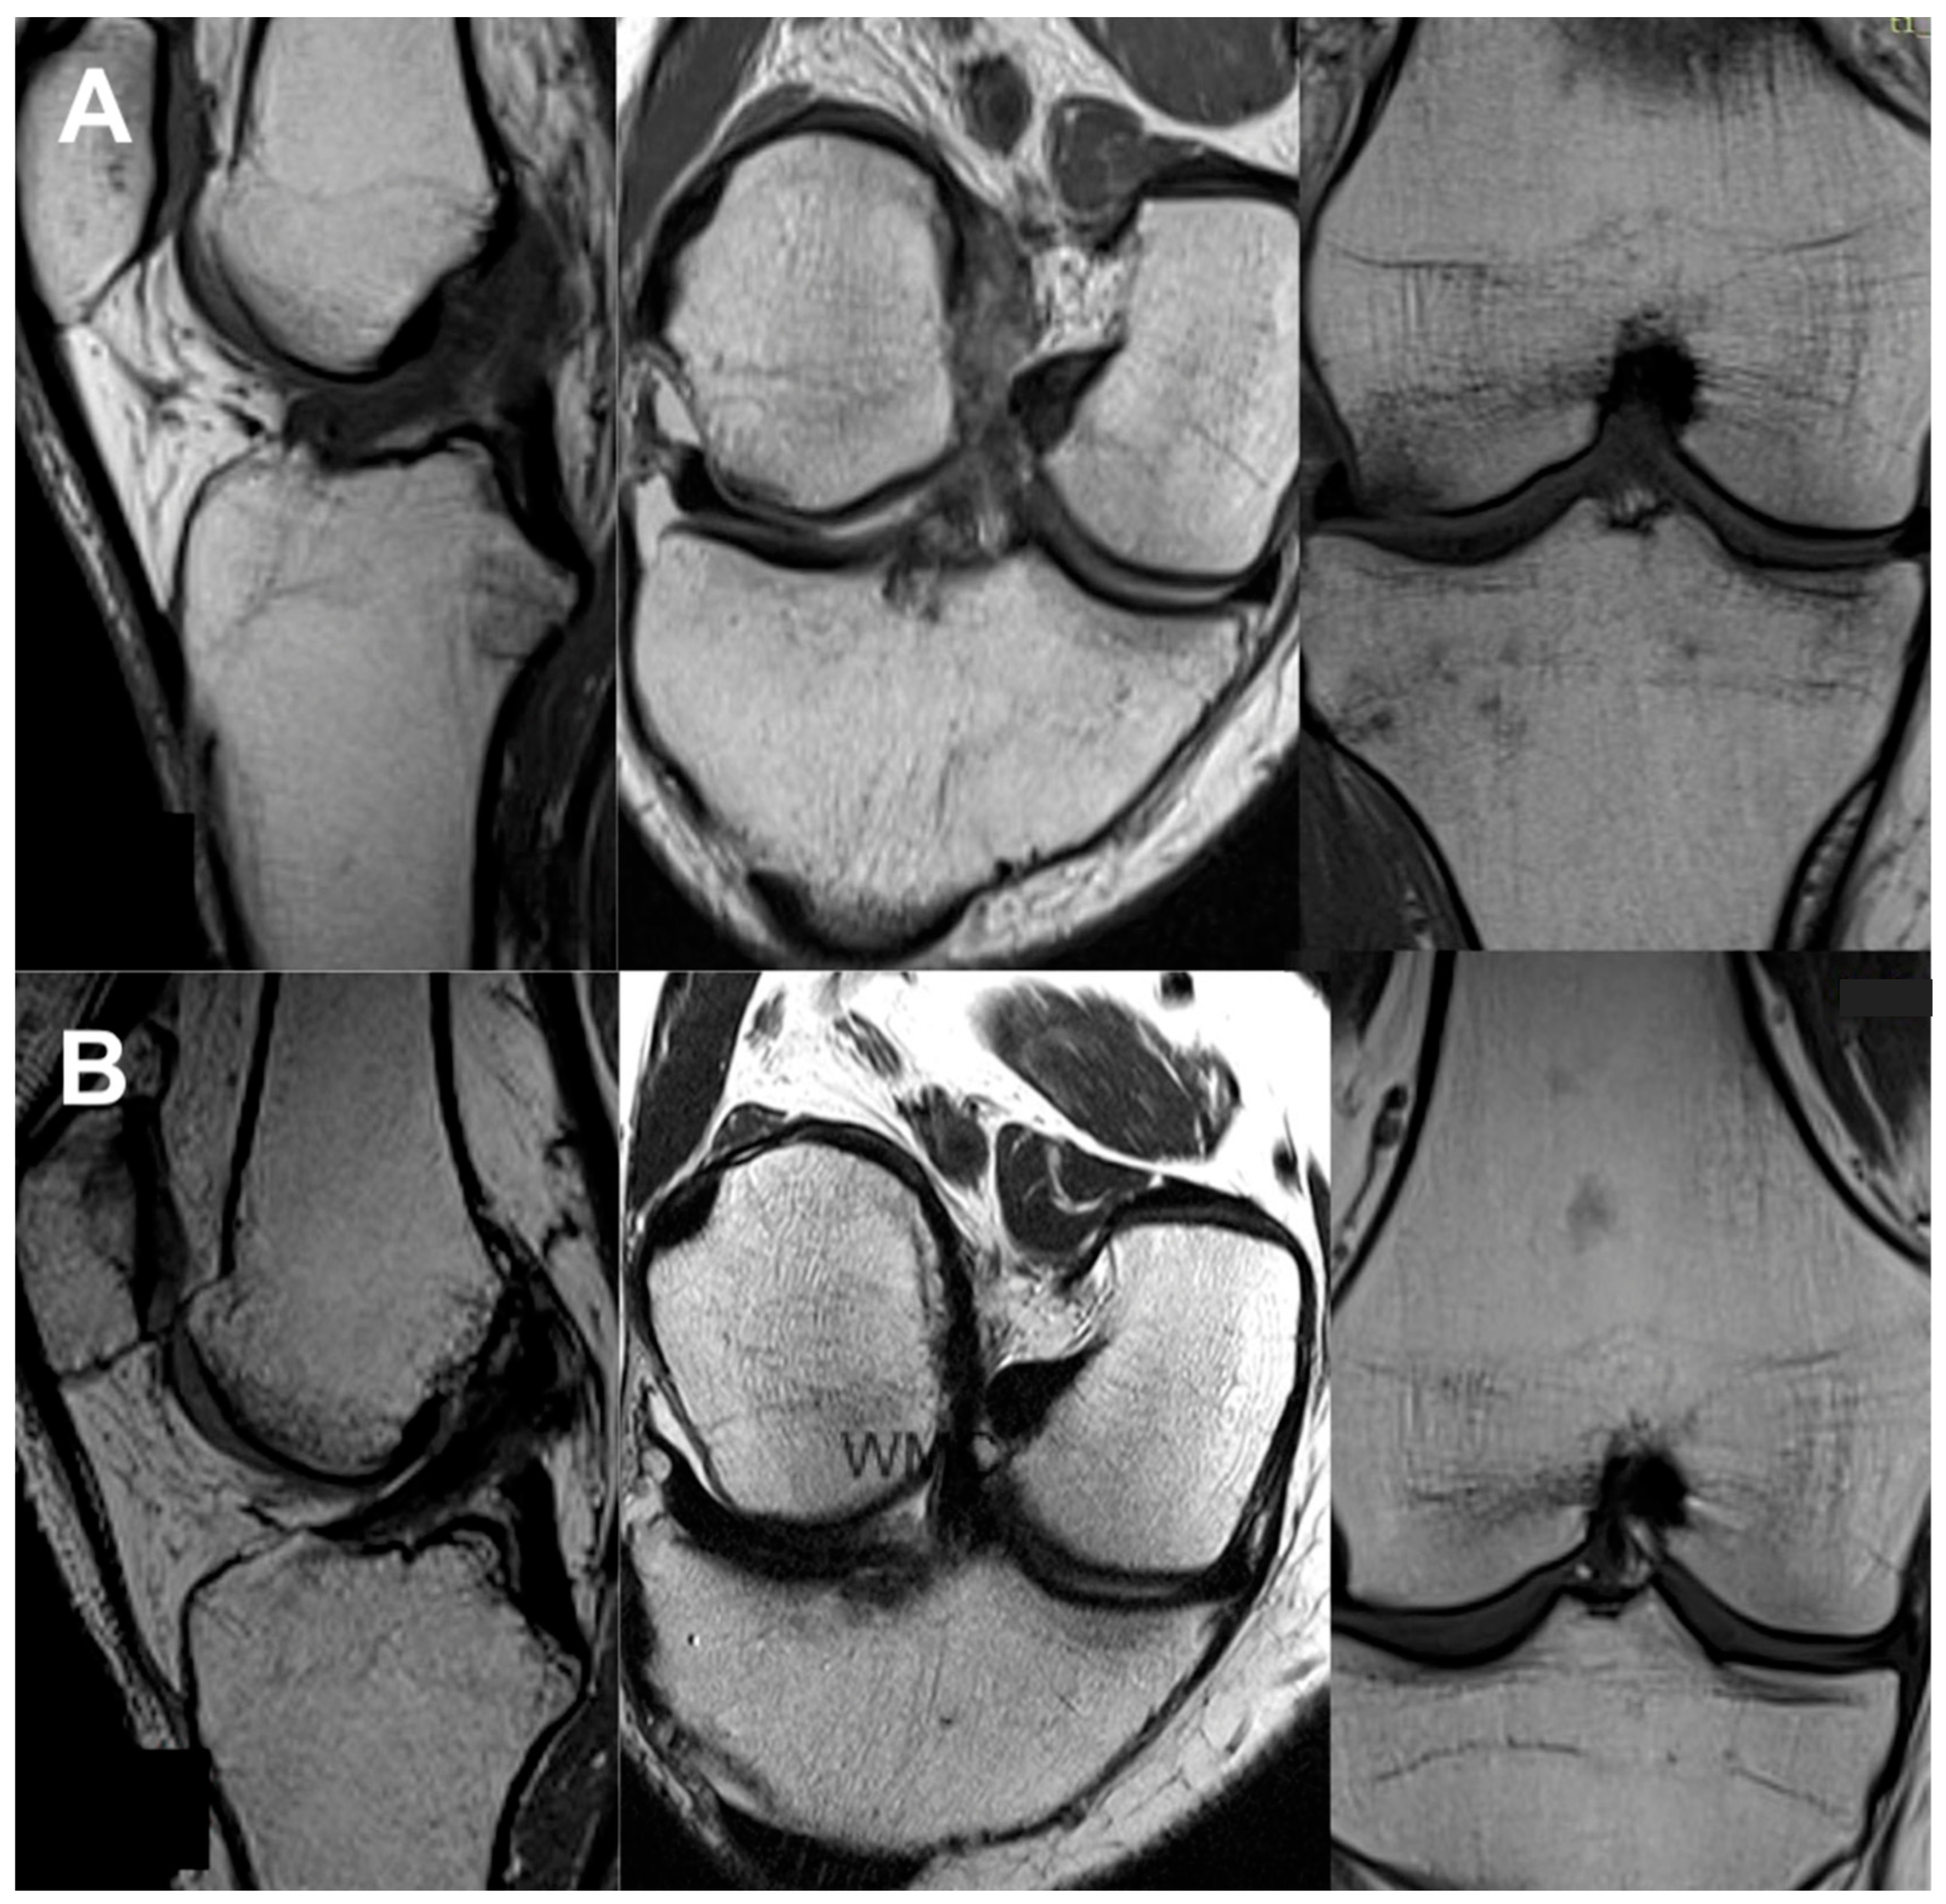

3.3. Imaging Analysis